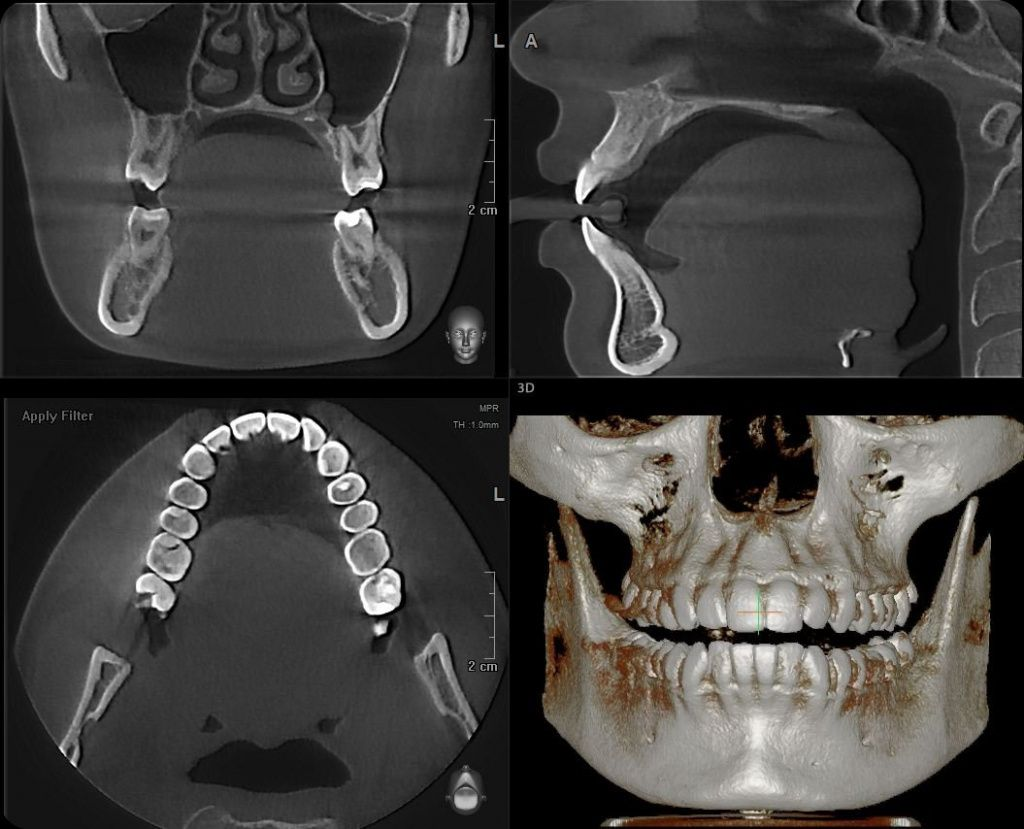

Компьютерная томография зубов — это современный метод рентгенологической диагностики, который позволяет получить трехмерное изображение зубов, челюстей и окружающих анатомических структур. В отличие от прицельных снимков и ортопантомограммы, КТ дает объемную картину без искажений.

На компьютерной томографии отчетливо визуализируются корни зубов, костная ткань челюсти, зачатки зубов, гайморовы пазухи и расположение нервных каналов. Это особенно важно при удалении дистопированных зубов, имплантации и лечении корневых каналов.

КТ позволяет оценить плотность кости, направление корней и степень воспалительных изменений, что напрямую влияет на выбор метода лечения.

Процедура занимает несколько минут и не требует специальной подготовки. Пациент фиксирует положение головы, после чего аппарат выполняет сканирование. Полученные данные обрабатываются программным обеспечением и формируют трехмерную модель челюстно-лицевой области. Врач анализирует изображение и использует его для планирования лечения.